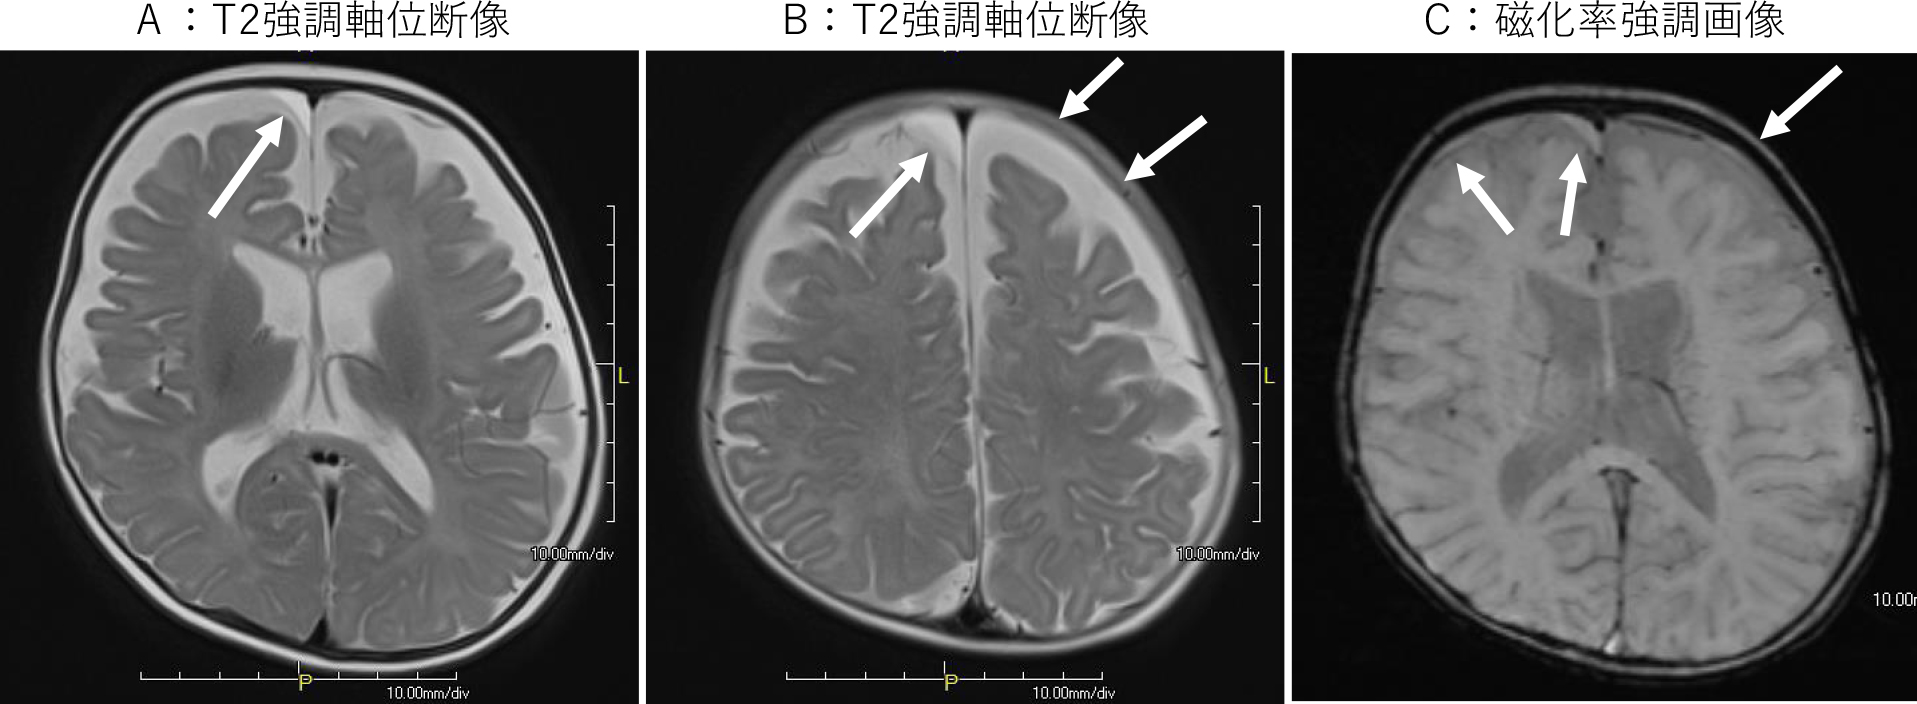

良性くも膜下腔開大症(BESS)症例に認めた非外傷性硬膜下液貯留腔(水腫)

5か月,男児.頭囲拡大.頭部外傷の既往なし.

A,B:T2強調軸位断像:両側前頭部頭蓋内板下に髄液より高信号を示す液貯留を認める(⇨).

C:磁化率強調軸位断像:液貯留腔は高信号を示し,蛋白濃度の高い内容液であることを示す.出血を示唆する低信号は認められない(⇨).